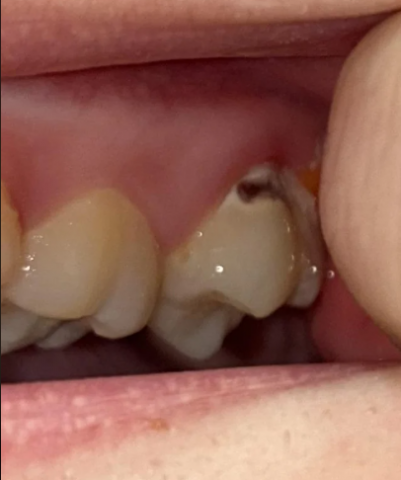

| Dark Spot | A significant, dark, black/brown area is visible on the upper/side of the tooth near the gum line. | Severe Dental Caries (Cavity): This indicates tooth decay, likely into the dentin, possibly approaching the pulp (nerve). |

| Yellowing | The surrounding tooth structure appears generally yellow/darker than the adjacent tooth. | Extrinsic Staining, Worn Enamel, or Exposed Dentin: While yellowing can be normal, if it is suddenly changing, it could mean the outer white enamel is thinning or has been removed by decay, exposing the naturally yellower dentin. |

| Gum Tissue | The gum tissue around the affected tooth appears slightly red/inflamed. | Gingivitis or Gum Irritation: Likely due to the proximity of the decay/plaque and/or poor brushing technique in the area. |

| Full Analysis & Diagnosis | Severe Dental Caries (Cavity), likely requiring immediate professional intervention. The decay appears deep and may extend to the pulp. The yellowing is likely secondary to this decay or exposed dentin. |